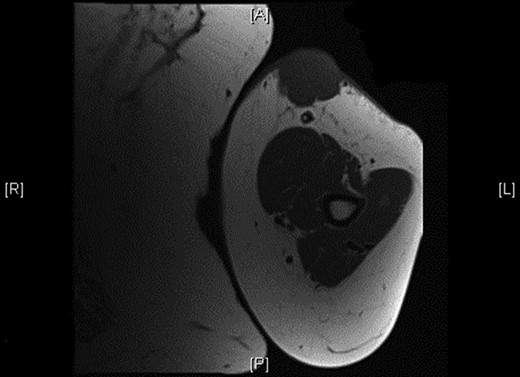

Physical examination revealed a 12 cm × 10 cm fungating soft tissue mass with no evidence of axillary or cervical lymphadenopathy. Following urgent magnetic resonance imaging of the lesion (Fig. 3), biopsies were obtained under local anaesthesia. Histology result identified an ulcerated and invasive tumour involving the dermis (Fig. 4). It was composed of sheets of monotonous atypical round cells with hyperchromatic nuclei. The tumour cells were positive for chromogranin, CD56 and CK20 and negative for S-100, TTF-1, LCA and Melan-A. These confirmed the diagnosis of MCC and the patient was thus treated with wide-local excision and radiotherapy. Further review at 6 months confirms the patient has had a good postoperative course and is free of local recurrence and distal metastases.

Shows the mass being superficial and subcutaneous without any underlying muscle involvement on magnetic resonance imaging.